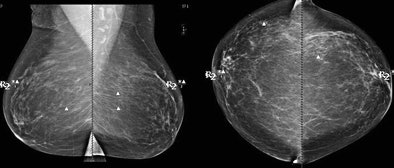

![]() |

| Above, CAD missed the subtle calcification near LCIS while marking several other regions. CAD marked the LCIS lesion on both views in the patient shown below. Images courtesy of Stamatia Destounis, MD. |